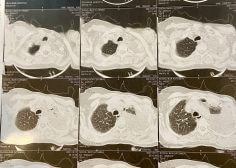

Left pulmonary malignancy and occlusion effect on LPA

Patient with left pulmonary malignancy and occlusion effect on LPA with low LVEF undergone tumor resection and PPM insertion.